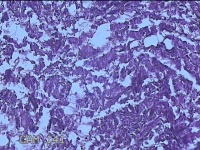

外阴部包块

性别

女

年龄

37岁

临床诊断

皮脂腺囊肿

一般病史

外阴部起包块一月余。

标本名称

大体所见

灰白暗红色包块2.3x1.8x0.8cm一个,表面糜烂,切开包块呈实性,切面灰白淡黄色,质软。

图4